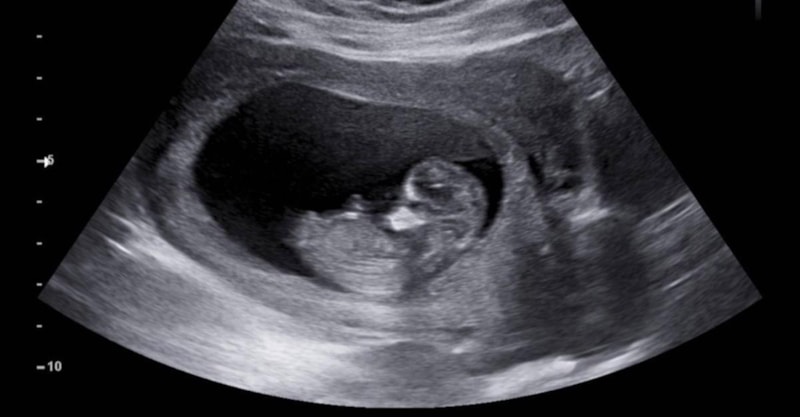

St. Jude Çocuk Araştırma Hastanesi'ndeki bilim insanları, ilk rahim içi tedaviye öncülük etti.

İlacı rahim içi olarak uygulama fikri ebeveynlerden geldi ve doktorlar, anneye ilacı hamileliğinin son 6 haftasında verdi.